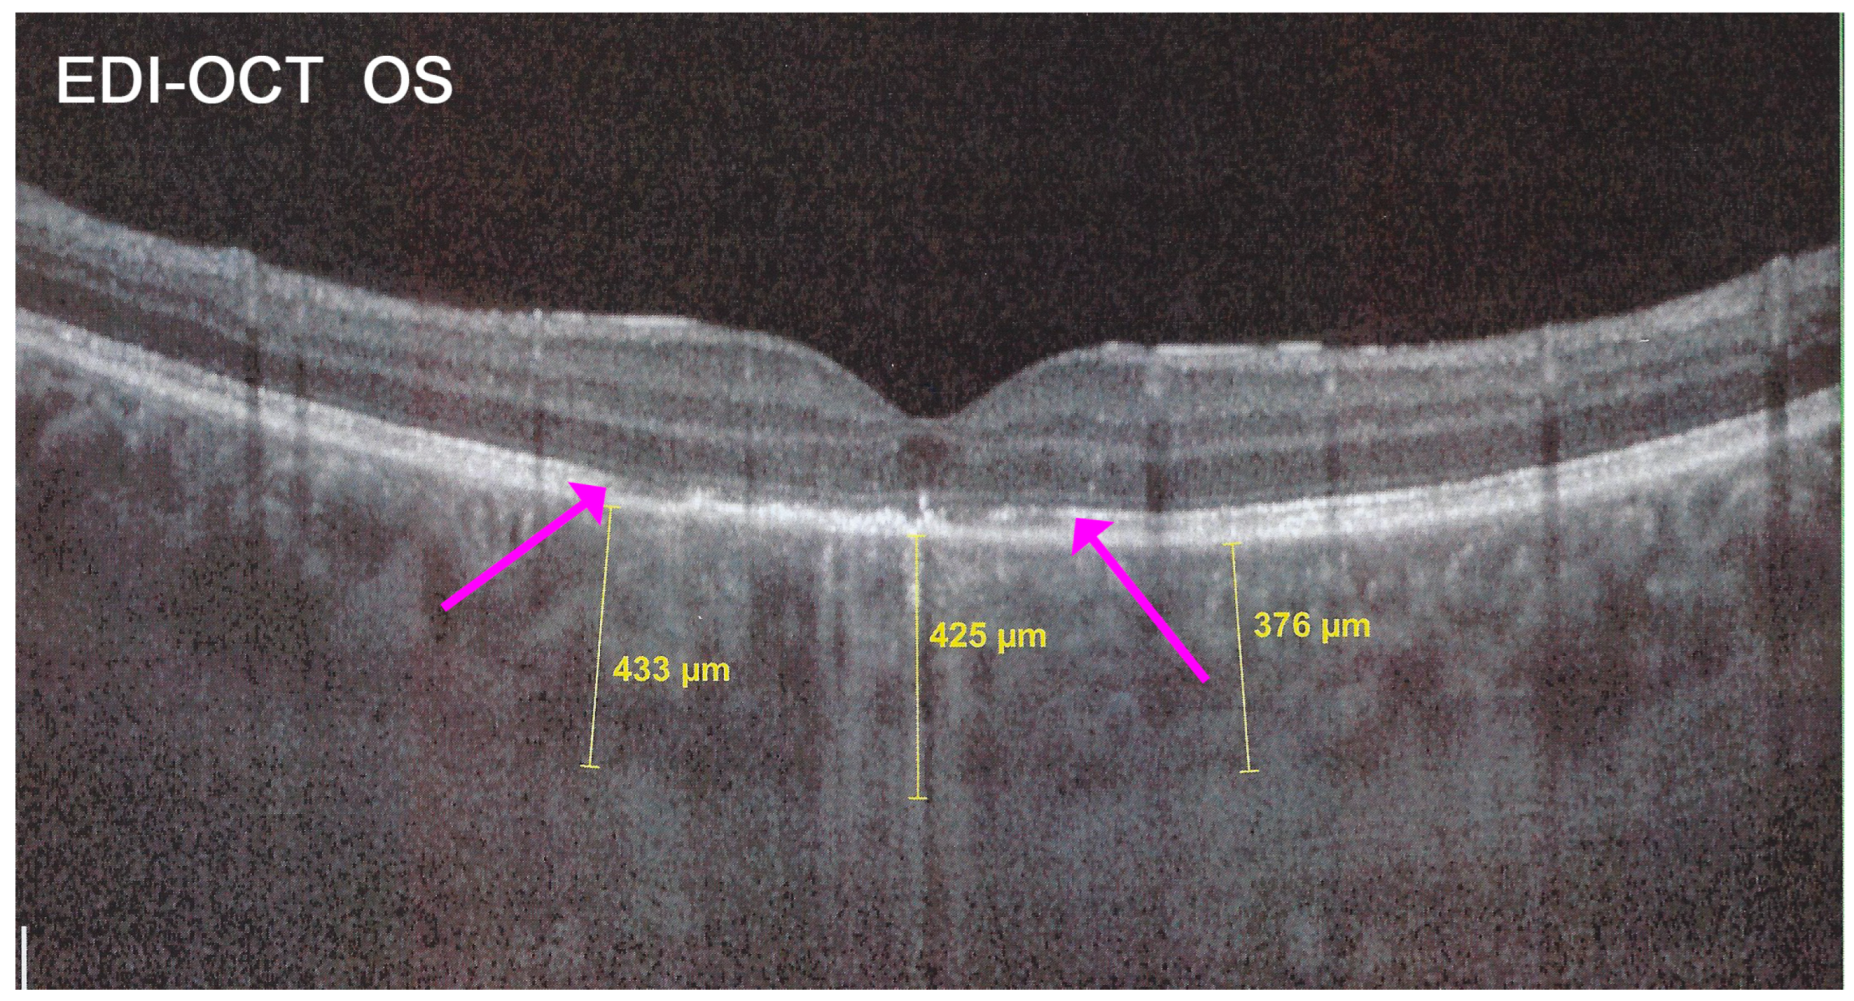

Figure 25. APMPPE/AMIC; EDI-OCT (same case as Figure 21 and Figure 22). Besides the loss of photoreceptor outer segments (marked by crimson arrows), the whole choroid is thickened, with callipers showing values between 376 µm and 433 µm.

In addition to choriocapillaris non-perfusion, in most acute cases, the entire choroid is thickened, which can be shown by enhanced depth imaging OCT (EDI-OCT) (Figure 11). In complement to ICGA, OCT angiography (OCT-A) shows areas of choriocapillary drop-out that correlate with the areas of ICGA hypofluorescence the analysed area being however, limited to part of the posterior pole and less precise than ICGA [5,7,25] (Figure 12).

The exact extensions of bilateral lesions were clearly delineated on ICGA showing scattered small hypofluorescent areas of choriocapillaris non-perfusion OD and more confluent hypofluorescent lesions OS (Figure 24), corresponding to areas of hyperautofluorescence on BL-FAF and FA hyperfluorescence (Figure 24). SD-OCT showed loss of photoreceptor outer segments and irregularity of the IS/OS line due to ischaemia following choriocapillaris non-perfusion (Figure 24). FA hyperfluorescence is explained by compensatory retinal exudation with limited pooling as the patient was already under corticosteroid therapy. Besides choriocapillaris non-perfusion, the whole choroidal thickness was increased (Figure 25).